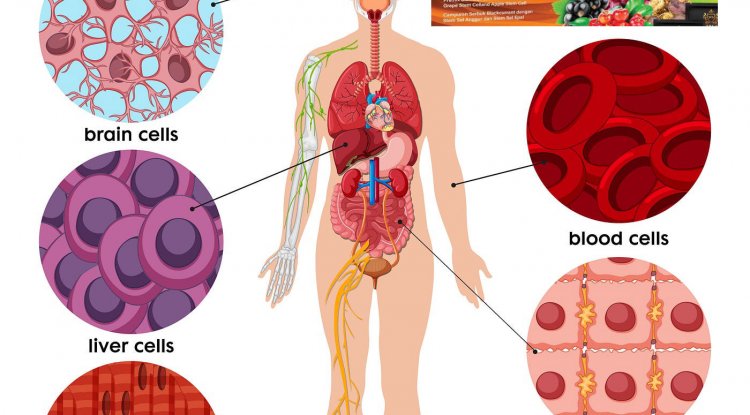

Normal adult stem cells have been defined for more than a half-century. Relatively rare, they are undifferentiated cells within a tissue that divide to produce two daughter cells. One remains in the stem cell state to maintain the stem cell population, a process called self-renewal. The second daughter cell adopts a partially differentiated state, then goes on to divide and differentiate further to yield multiple cell types that form that tissue. In many fully formed adult tissues, normal stem cells divide periodically to replenish or repair the tissue. Importantly, this division is a carefully controlled process to ensure that tissues are restricted to the appropriate size and cell content.

Cancer stem cells are also of long-standing interest and share many similarities with normal adult stem cells. They perform the same division but, rather than differentiating, the additional cells produced by the second daughter cell amass to form the bulk of the tumor. Following surgery or treatment, cancer stem cells can regrow the tumor — and are frequently resistant to chemotherapy — making them especially dangerous. This unique ability of normal and cancer stem cells to both self-renew and form a tissue or tumor is referred to by researchers as “stemness,” and has important implications for biomedical applications.

One of the fundamental challenges to studying normal and cancer stem cells, and to ultimately harnessing that knowledge, is developing the ability to identify, purify, and propagate these cells. This has often proved tricky, as another key similarity between normal and cancer stem cells is that neither is visibly different from other cells in a tissue or tumor. Thus, a major goal in stem cell and cancer stem cell research is finding ways to distinguish these rare specimens from other cells, ideally by identifying unique surface markers that can be used to purify stem cell and cancer stem cell populations and enable their study.